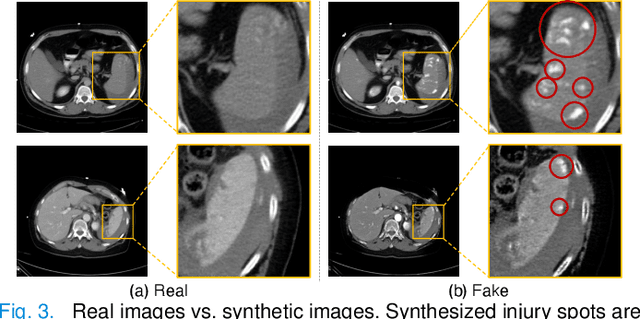

Abstract:The spleen is one of the most commonly injured solid organs in blunt abdominal trauma. The development of automatic segmentation systems from multi-phase CT for splenic vascular injury can augment severity grading for improving clinical decision support and outcome prediction. However, accurate segmentation of splenic vascular injury is challenging for the following reasons: 1) Splenic vascular injury can be highly variant in shape, texture, size, and overall appearance; and 2) Data acquisition is a complex and expensive procedure that requires intensive efforts from both data scientists and radiologists, which makes large-scale well-annotated datasets hard to acquire in general. In light of these challenges, we hereby design a novel framework for multi-phase splenic vascular injury segmentation, especially with limited data. On the one hand, we propose to leverage external data to mine pseudo splenic masks as the spatial attention, dubbed external attention, for guiding the segmentation of splenic vascular injury. On the other hand, we develop a synthetic phase augmentation module, which builds upon generative adversarial networks, for populating the internal data by fully leveraging the relation between different phases. By jointly enforcing external attention and populating internal data representation during training, our proposed method outperforms other competing methods and substantially improves the popular DeepLab-v3+ baseline by more than 7% in terms of average DSC, which confirms its effectiveness.